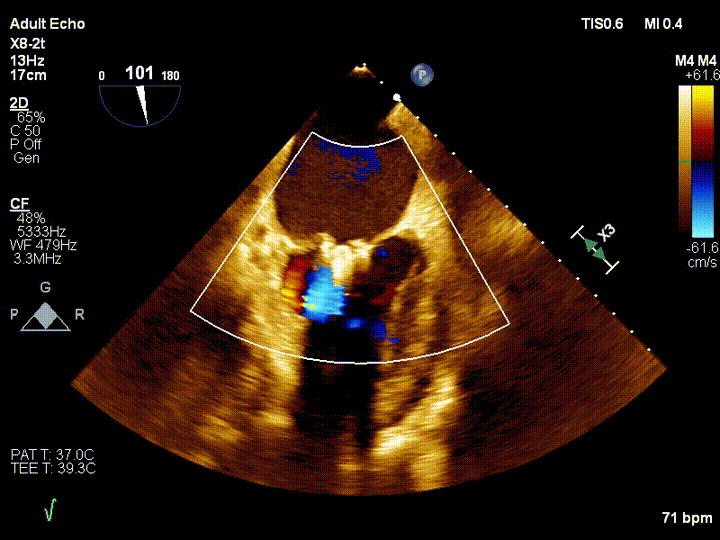

该患者是一名71岁老人,反复气喘3年余,加重3周余。入院诊断为二尖瓣后叶脱垂伴重度关闭不全,超声心动图提示:二尖瓣后叶脱垂伴重度关闭不全。该患者同时合并冠心病、房颤、外周动脉硬化、肾功能不全等疾病,心脏团队评估患者开胸手术风险极高,微创二尖瓣修复手术是最适合的治疗方式,因此患者及家属充分考虑后选择该项技术治疗,并签署本研究知情同意书,王焱教授团队全面评估后确认该患者符合本研究入选标准,注册入选成为福建省第一个入组治疗的患者。

王焱教授团队和美国弗吉尼亚大学医学中心David Scott Lim教授、香港亚心医院林逸贤教授术前详细评估并制定了相应的手术策略,并在手术当天在线指导。在浙江大学附属第二医院王建安书记结构团队核心成员刘先宝主任的现场指导下,王焱院长团队顺利完成股静脉穿刺,然后在食道超声指引下顺利穿刺理想位置的房间隔,肝素化后,放置25F鞘管至左房,测定左房压,随后顺利于二尖瓣前后叶植入两枚二尖瓣钳夹装置,术前患者二尖瓣重度反流即刻减轻至微量,左房压力即刻减低,预示着患者的临床症状将得到明显改善。手术全程用时不到2小时,患者术后即刻拔管苏醒。